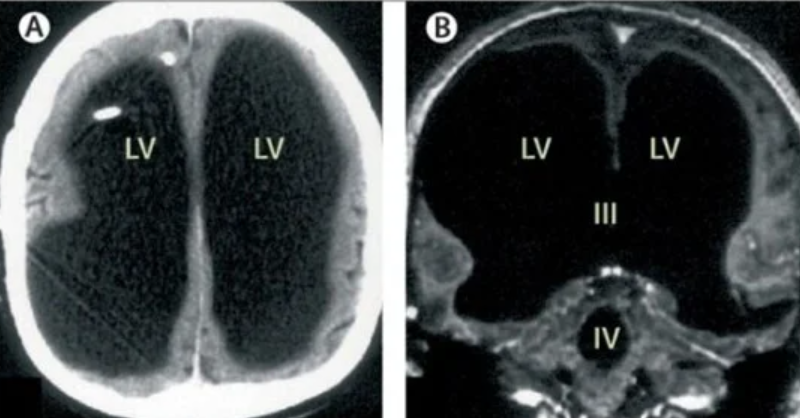

Историята започва с това, че французинът се оплаквал от болки в крака, когато посетил доктор. Изпратили го на пълни изследвания и скенерът показал невероятното откритие – черепът му бил запълнен почти изцяло с течност, оставяйки тънък слой мозъчна тъкан.

Докторите смятат, че с времето по-голямата част от мозъка му бавно се е разрушавала от течността. Това заболяване се нарича хидроцефалия. Диагнозата е била поставена на мъжа още като дете и бил лекуван с поставянето на стент, но излишната течност продължила да се натрупва, измествайки мозъчното вещество.